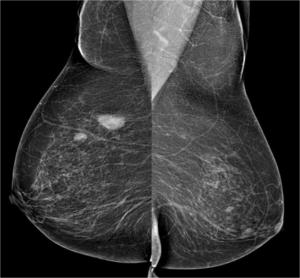

Mammography

38 year old lady with right breast lump of one year duration...

Read More